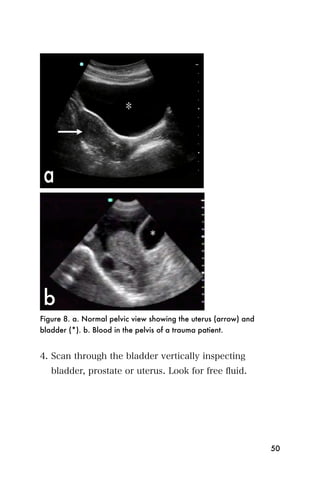

Figure 8. a. Normal pelvic view showing the uterus (arrow) and

bladder (*). b. Blood in the pelvis of a trauma patient.

4. Scan through the bladder vertically inspecting

bladder, prostate or uterus. Look for free fluid.